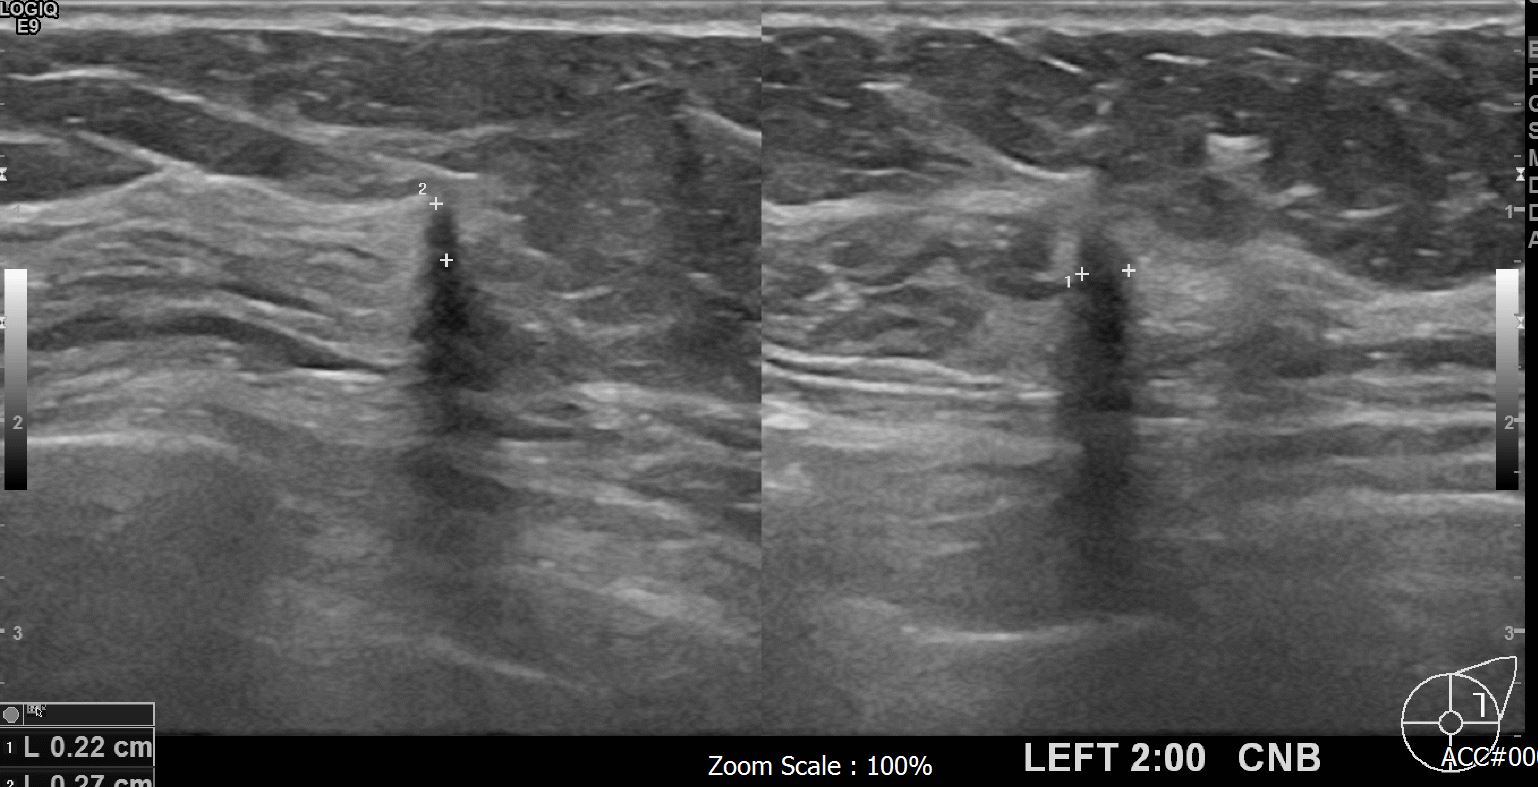

상기환자 외부검사상 이상소견으로 내원하신 60대 여성분으로

좌측의 의심스런혹 조직검사 시행해 유방암 진단되었읍니다